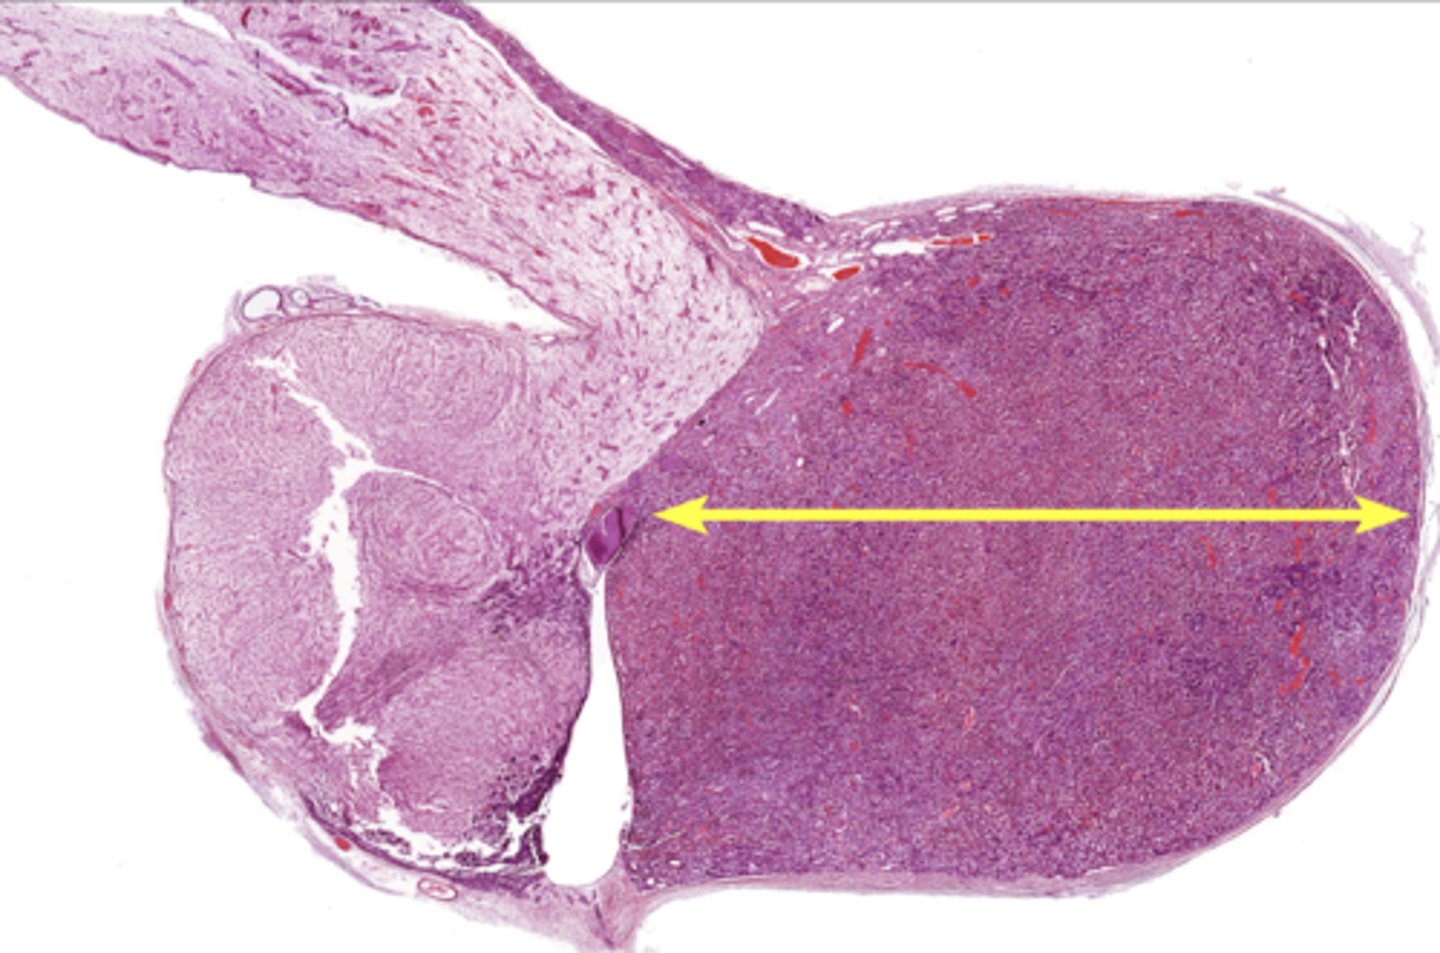

Thymus

Pancreas

Pancreatic islet

Adrenal gland

Adrenal cortex

Zona glomerulosa

Zona fasciculata

Zona reticularis

Adrenal medulla